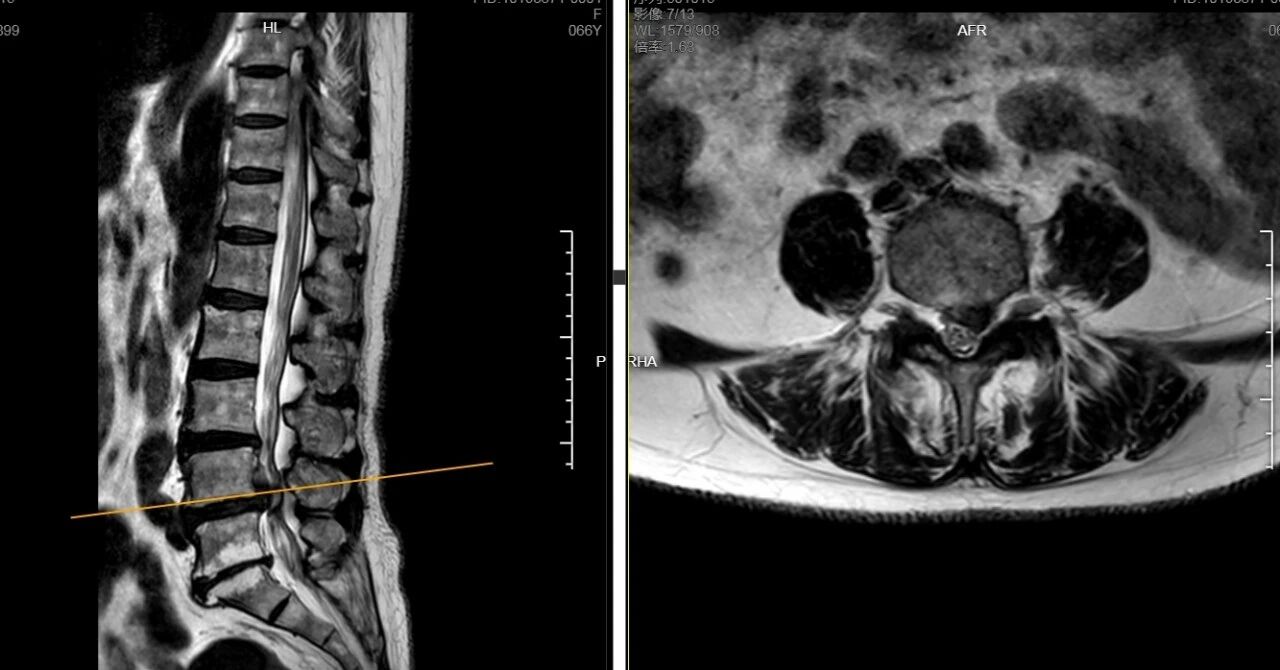

顾女士长期被腰椎间盘脱出导致臀部及左下肢的放射性疼痛缠扰,她辗转多家医院,尝试过多种保守治疗,症状却愈发严重,不仅让她“坐立难安”,生活质量也大打折扣。近日,深受病痛之苦的顾女士慕名来到南通市第三人民医院脊柱外科,经腰椎CT及MRI检查,其L4—L5椎间盘突出,神经根受压严重,综合评估目前仅靠保守治疗已难以解决病痛的折磨,脊柱外科专家团队最终决定采用业内领先的AUSS微创手术为患者解除病痛。